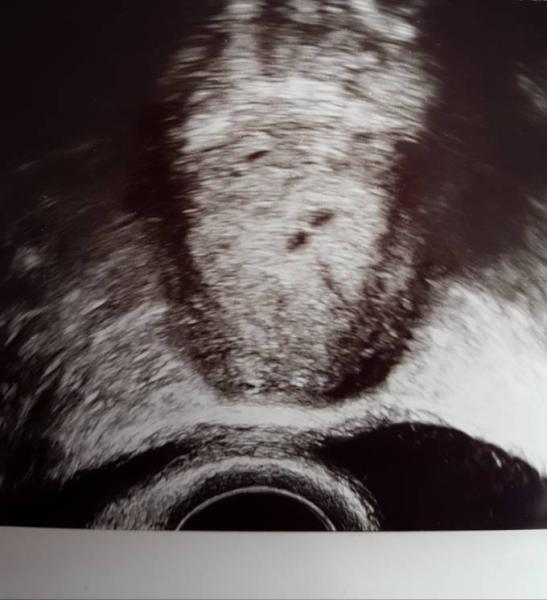

Ja waren Zwillis eigtl.. ich schick euch mal wieder das Bild von Freitag. Die vom KH meinte sogar 3 FH zu sehen, jeden Tag was anderes oder neues. Ich höre garnicht mehr drauf die machen einen verrückt.. Aber danke für die aufmunternten Antworten, iwie sagt mir ein Gefühl, dass ich morgen eine gute Nachricht kriegen werde obwohl ich schon keine Hoffnungen mehr hab

Bild zu